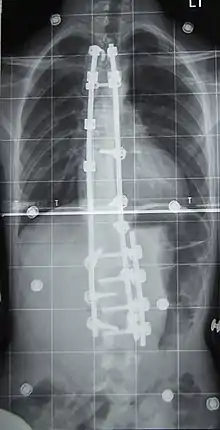

Surgery

Surgery is usually recommended by orthopedists for curves with a high likelihood of progression (i.e., greater than 45–50° of magnitude), curves that would be cosmetically unacceptable as an adult, curves in people with spina bifida and cerebral palsy that interfere with sitting and care, and curves that affect physiological functions such as breathing.[101][102]

Surgery is indicated by the Society on Scoliosis Orthopaedic and Rehabilitation Treatment (SOSORT) at 45–50°[4] and by the Scoliosis Research Society (SRS) at a Cobb angle of 45°.[103] SOSORT uses the 45–50° threshold as a result of the well-documented, plus or minus 5° measurement error that can occur while measuring Cobb angles.[103]

Surgeons who are specialized in spine surgery perform surgery for scoliosis. To completely straighten a scoliotic spine is usually impossible, but for the most part, significant corrections are achieved.[104]

The two main types of surgery are:[105]

- Anterior fusion: This surgical approach is through an incision at the side of the chest wall.

- Posterior fusion: This surgical approach is through an incision on the back and involves the use of metal instrumentation to correct the curve.

One or both of these surgical procedures may be needed. The surgery may be done in one or two stages and, on average, takes four to eight hours.

Treatment for idiopathic scoliosis also depends upon the severity of the curvature, the spine's potential for further growth, and the risk that the curvature will progress. Mild scoliosis (less than 30° deviation) and moderate scoliosis (30–45°) can typically be treated conservatively with bracing in conjunction with scoliosis-specific exercises.[4] Severe curvatures that rapidly progress may require surgery with spinal rod placement and spinal fusion. In all cases, early intervention offers the best results.